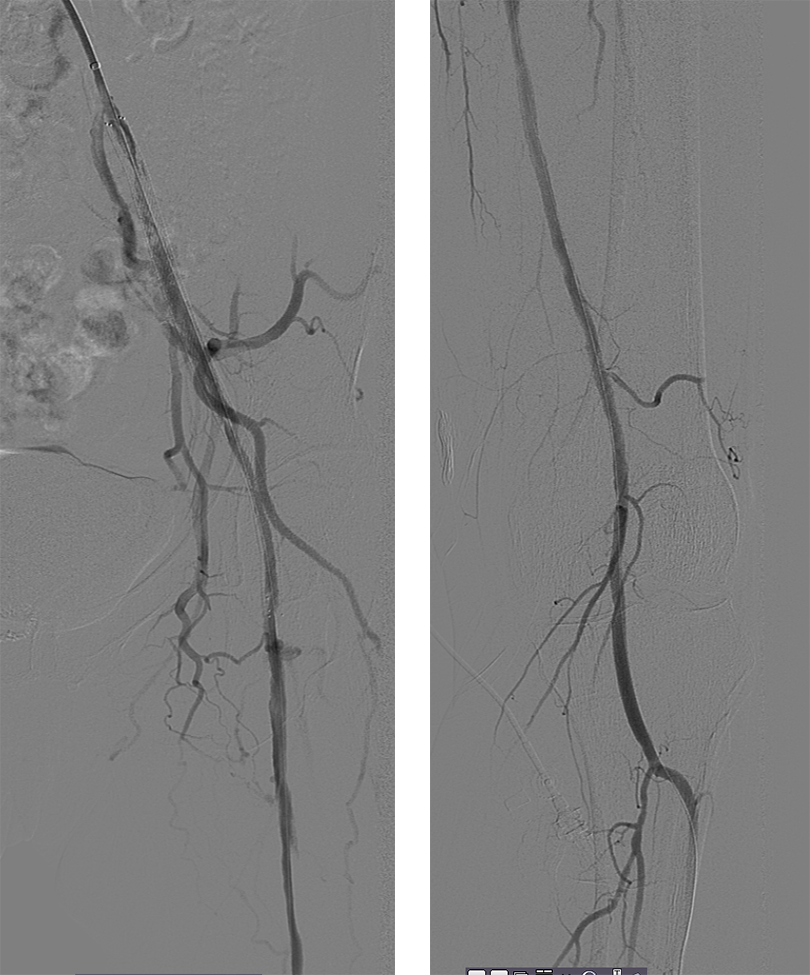

2、完善下肢动脉CTA提示:左侧髂动脉血栓栓塞,左股浅动脉多发狭窄。

顺行穿刺无法开通,行左侧腘动脉逆行穿刺,超选进入顺行导管。

球囊扩张全程血管,显示支架内有陈旧性血栓,予6F导管吸栓,最后造影显示血流较前通畅,部分附壁血栓继续抗凝治疗,定期随诊。予Exoseal封堵穿刺点。